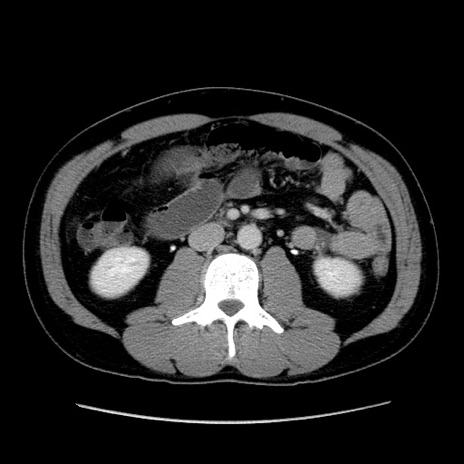

症例4(横断像)

【症例】30歳代男性

【主訴】腹痛、嘔吐

【現病歴】昨晩から突然の腹痛あり、その後嘔吐、軟便も出現。腹痛が改善しないため救急搬送となる。2日前にしめ鯖の食事歴あり。

【身体所見】意識清明、苦悶様、BP 135/90mmHg、BT 35.7℃、腹部:平坦、やや硬、心窩部〜臍部に自発痛、圧痛あり、筋性防御+、反跳痛-

【データ】WBC 8100、CRP 0.57